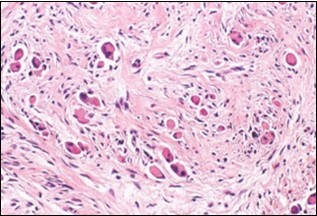

On microscopy, a collagen- rich, minimally cellular, fibrotic soft tissue nodule is exemplified which simulates a scar or conventional fibroma. The neoplasm is comprised of uniform, plump, fibroblastic or myo-fibroblastic cells encompassed in a collagen-rich stroma with infiltration and entrapment of skeletal myocytes 5, 6. Cogent histological examination depicts replacement of muscle fibres and muscle mass with fascicles of fibrous tissue comprised of mature fibroblastic cells, thereby conferring fibrosis 6. Figure 1, Figure 2, Figure 3, Figure 4, Figure 5, Figure 6, Figure 7, Figure 8.

Figure 3.Fibromatosis colli depicting fascicles of fibroblasts and myo-fibroblasts admixed with a collagenous stroma and extravasation of numerous red blood cells 10.

Figure 6.Fibromatosis colli depicting clusters of spindle-shaped cells, plump fibroblasts and comingled mature skeletal muscle fibres with collagen-rich stroma 13.